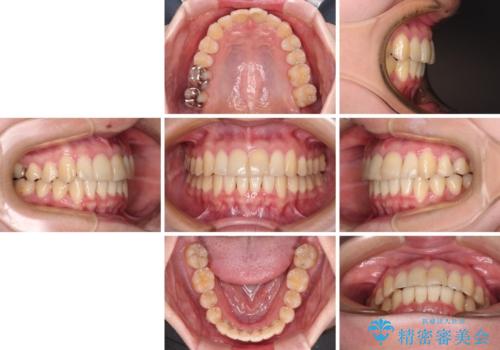

上下前歯のデコボコをきれいに インビザラインによる矯正治療

ワイヤー矯正を併用したことで前歯の叢生を速やかに解消することができました。

一方口元の突出感を改善するために時間がかかり、2年超を要しましたが、満足のいく仕上がりとなりました。